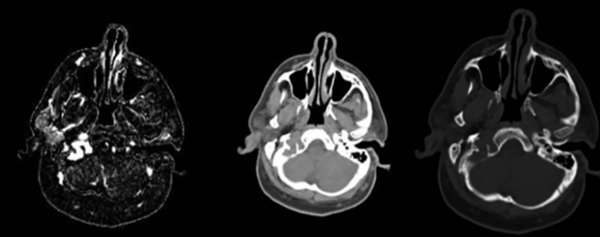

Un paciente varón de 51 años de edad, consultó por presentar quemosis, exoftalmo y dolor ocular de intensidad 2/10 de un año de evolución (Figura 1). Se realizó una tomografía computada (TC) de órbita que evidenció exoftalmia derecha, elongación de los músculos extrínsecos y del nervio óptico, e ingurgitación de los vasos intraorbitarios. La TC de cerebro simple evidenció una imagen hipodensa de bordes irregulares y erosión ósea a nivel del foramen yugular y del canal del hipogloso derecho, que medía 15 por 28 mm. La angioTC objetivó el llenado de toda la lesión (Figura 2). Los diagnósticos diferenciales incluían: tumor metastásico, glomus yugular, schwannoma y malformación vascular. La TC de tórax, abdomen y pelvis descartó la presencia de tumores. Para completar el estudio se le realizó una angiografía digital cerebral que evidenció una malformación arteriovenosa con llenado venoso precoz localizada en la base del cráneo, con aferencias de ramos de la arteria faríngea ascendente, occipital y auricular posterior derecha, y de la arteria faríngea ascendente izquierda. Presentaba dos tipos de drenaje: uno anterógrado al bulbo yugular derecho, y otro retrógrado hacia la vena oftálmica superior derecha, a través del seno petroso inferior (SPI) y del seno cavernoso derecho (Figura 3 a y b).

Figura 2. De izquierda a derecha: TC sin contraste que muestra una lesión isodensa localizada en la base del cráneo, en el centro: la ventana ósea de TC objetiva la presencia de erosión ósea a nivel del cóndilo occipital derecho, a la derecha la angiotomografía cerebral evidencia una lesión hipervascularizada localizada a nivel del canal del hipogloso.